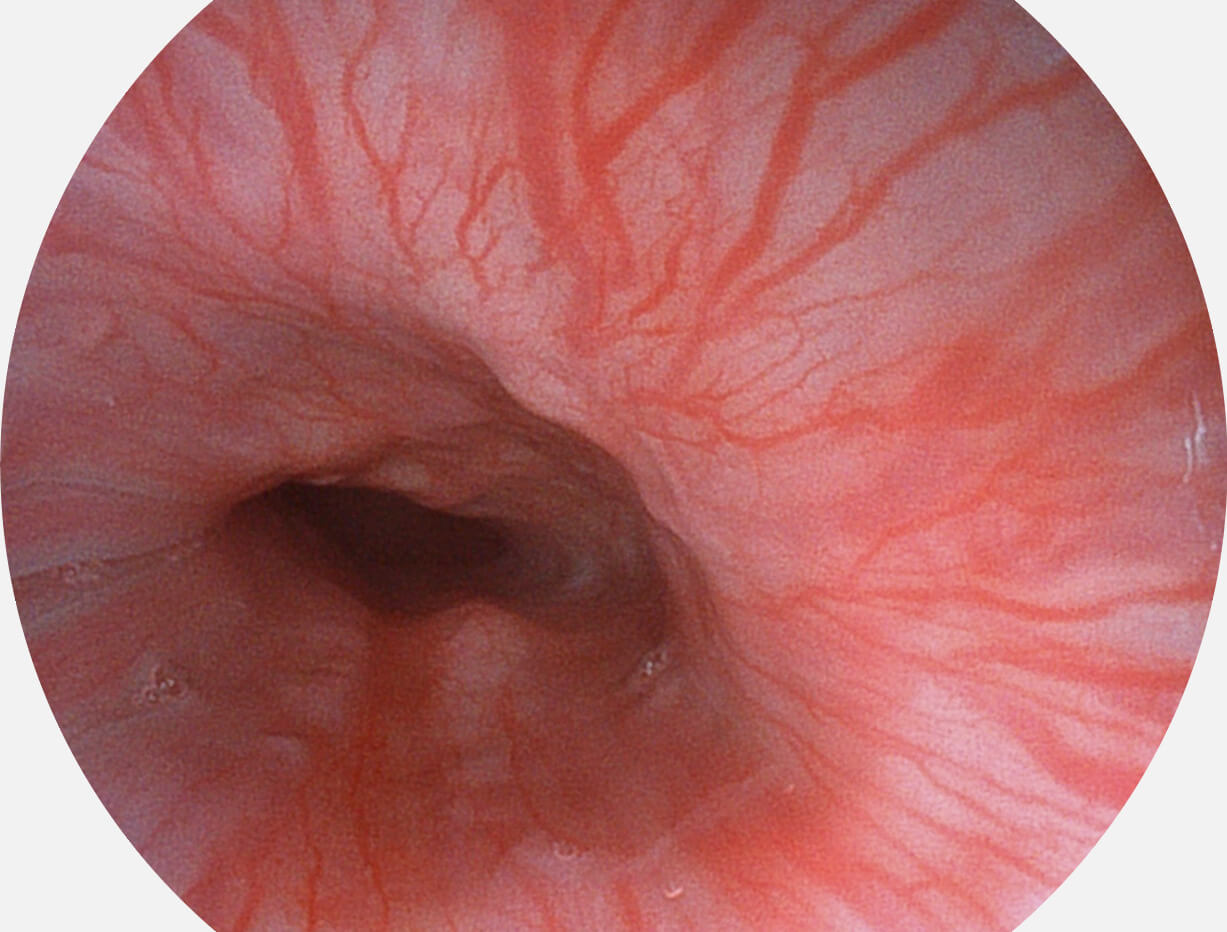

白光图像

SFI图像

Spectral Focused lmaging, SFI

图像具有高亮度、高黏膜血管颜色对比度的特点,且不改变粘液、食物残渣、粪便的基本颜色,可在中远景下进行观察,助力消化道早期疾病的诊断。